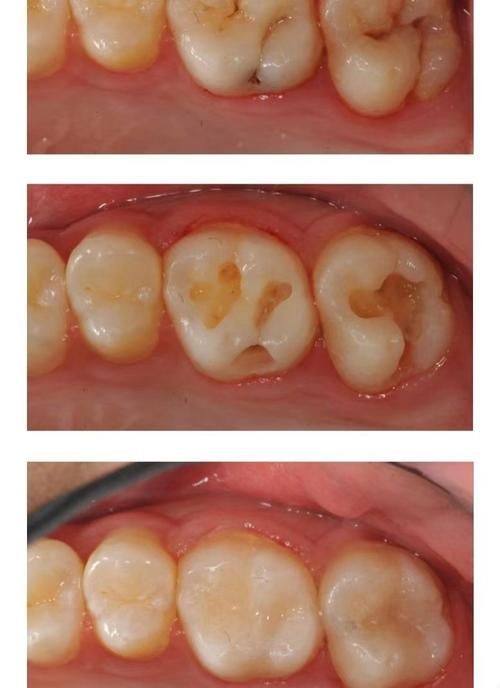

- 复合树脂和玻璃离子水门汀:这是目前常用的牙齿填充物,可以持续数年至数十年。复合树脂就像是一种“万能胶”,它能良好地贴合牙齿,而且颜色和牙齿比较接近,美观度较高。玻璃离子水门汀则具有一定的防龋作用,就像给牙齿加了一层保护罩。它们的持久性也不错,能满足大多数患者的需求。